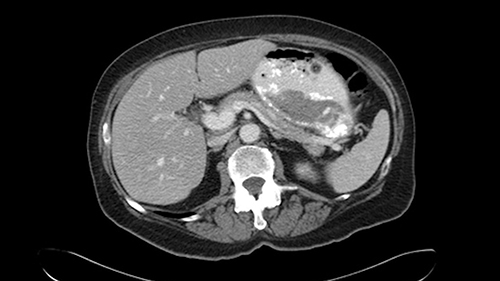

So we’re starting down here: right kidney Segment 6, and you can see there is a first lesion there. It’s probably in 5. I can’t say definitively just yet. That’s the lesion at the back it’s probably in Sg6.

Coming up a little bit higher. There’s a little bit of biliary dilatation as well. On the right side of the liver. Which may be nothing but it may be an indicator or harbinger of nodal disease in the hepatoduodenal ligament so something to be aware of. If the enzymatic liver function tests are normal and there’s no evidence of a stone in the common bile duct on cross sectional imaging you wouldn’t need to do anything about it but just to be aware of that.![[RHV]](jpg/preop_as_p4.jpg)

So we’re going through the liver segments now. Here we’ve got the inflow; here’s the main portal vein, right anterior sectoral portal vein, right posterior sectoral portal vein there. Here’s the main here going to the left lobe first of all. So that’s 3 and 2 there, they look clear, and there’s a good size of the left lobe with a good girth. So 3 and 2 look clear. There are usually more feedback branches from the left portal vein to segment 4b but that also looks relatively clear. There’s a little more disease over on the right side there. So that would be...right hepatic vein here...that’s Segment 7. So we’ve got disease in 7, 5, probably in 6 on the right side; at least 3 lesions. That’s the distribution of the lesions.![[Ant. RPV] [Main PV] [Post. RPV]](jpg/preop_as_p5.jpg)

So look at the MR from two points of view, firstly distribution of the lesions, secondly what kind of parenchyma would need to be resected to remove that disease and what kind of operation would we plan. And again so what we’re planning here would probably be a right hepatectomy. We know that there is plenty of disease-free left lobe. Segment 4 looks nice and clear. So a transection line coming down to about that kind of area would clear all of the disease. So that’s the kind of preoperative planning that we’d need to do.